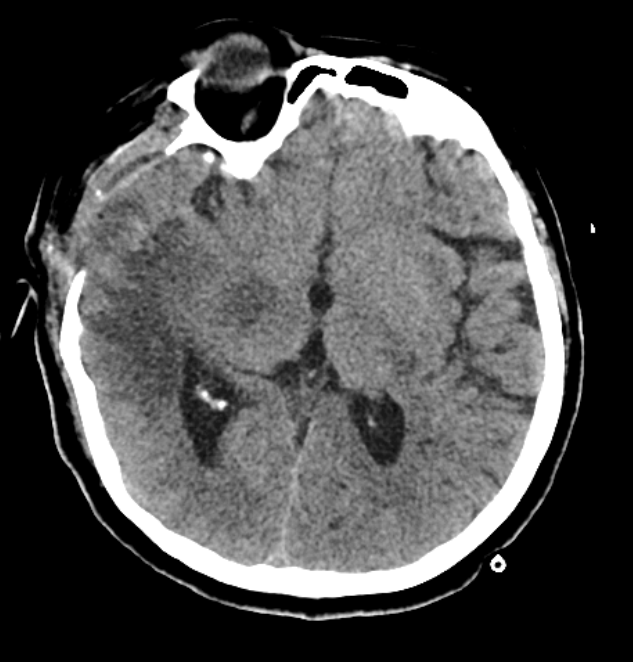

(下图左为患者术前出血照片,右为术后照片)

“患者入ICU后,一直处于昏迷状态,给予呼吸机支持治疗、后根据病情给予气管切开氧疗等辅助治疗......”ICU主治大夫高志英谈到。 24小时不间断对生命的执着守护,大家没有放弃,患者也没有放弃。“别拿被子压我,我难受。我要喝酸奶......”5天之后,在重症医护团队的全力救治下,这个年轻的生命终于奇迹般地苏醒了。医护人员欢欣鼓舞,这一刻,所有的坚持努力和辛苦付出都是值得的!“患者恢复的很好,这超出了我们的预料,当然也感到无比欣慰!”杨永春主任微笑着说道。

不久,患者顺利转入康复科,进一步接受康复治疗。她脸上露出了久违的笑容,遇到熟人,依然可以清晰地回忆往事,和大家愉快地交谈。 “我无法用语言表达自己的感激之情,中心医院医护人员给了我爱人无微不至的关怀,不仅用高超的医术挽救了她的生命,更用家人般的关爱温暖着我们的心,谢谢......”患者爱人激动地说道,他的声音有些哽咽,但眼里闪烁的泪光,映射出无限的温暖和喜悦。